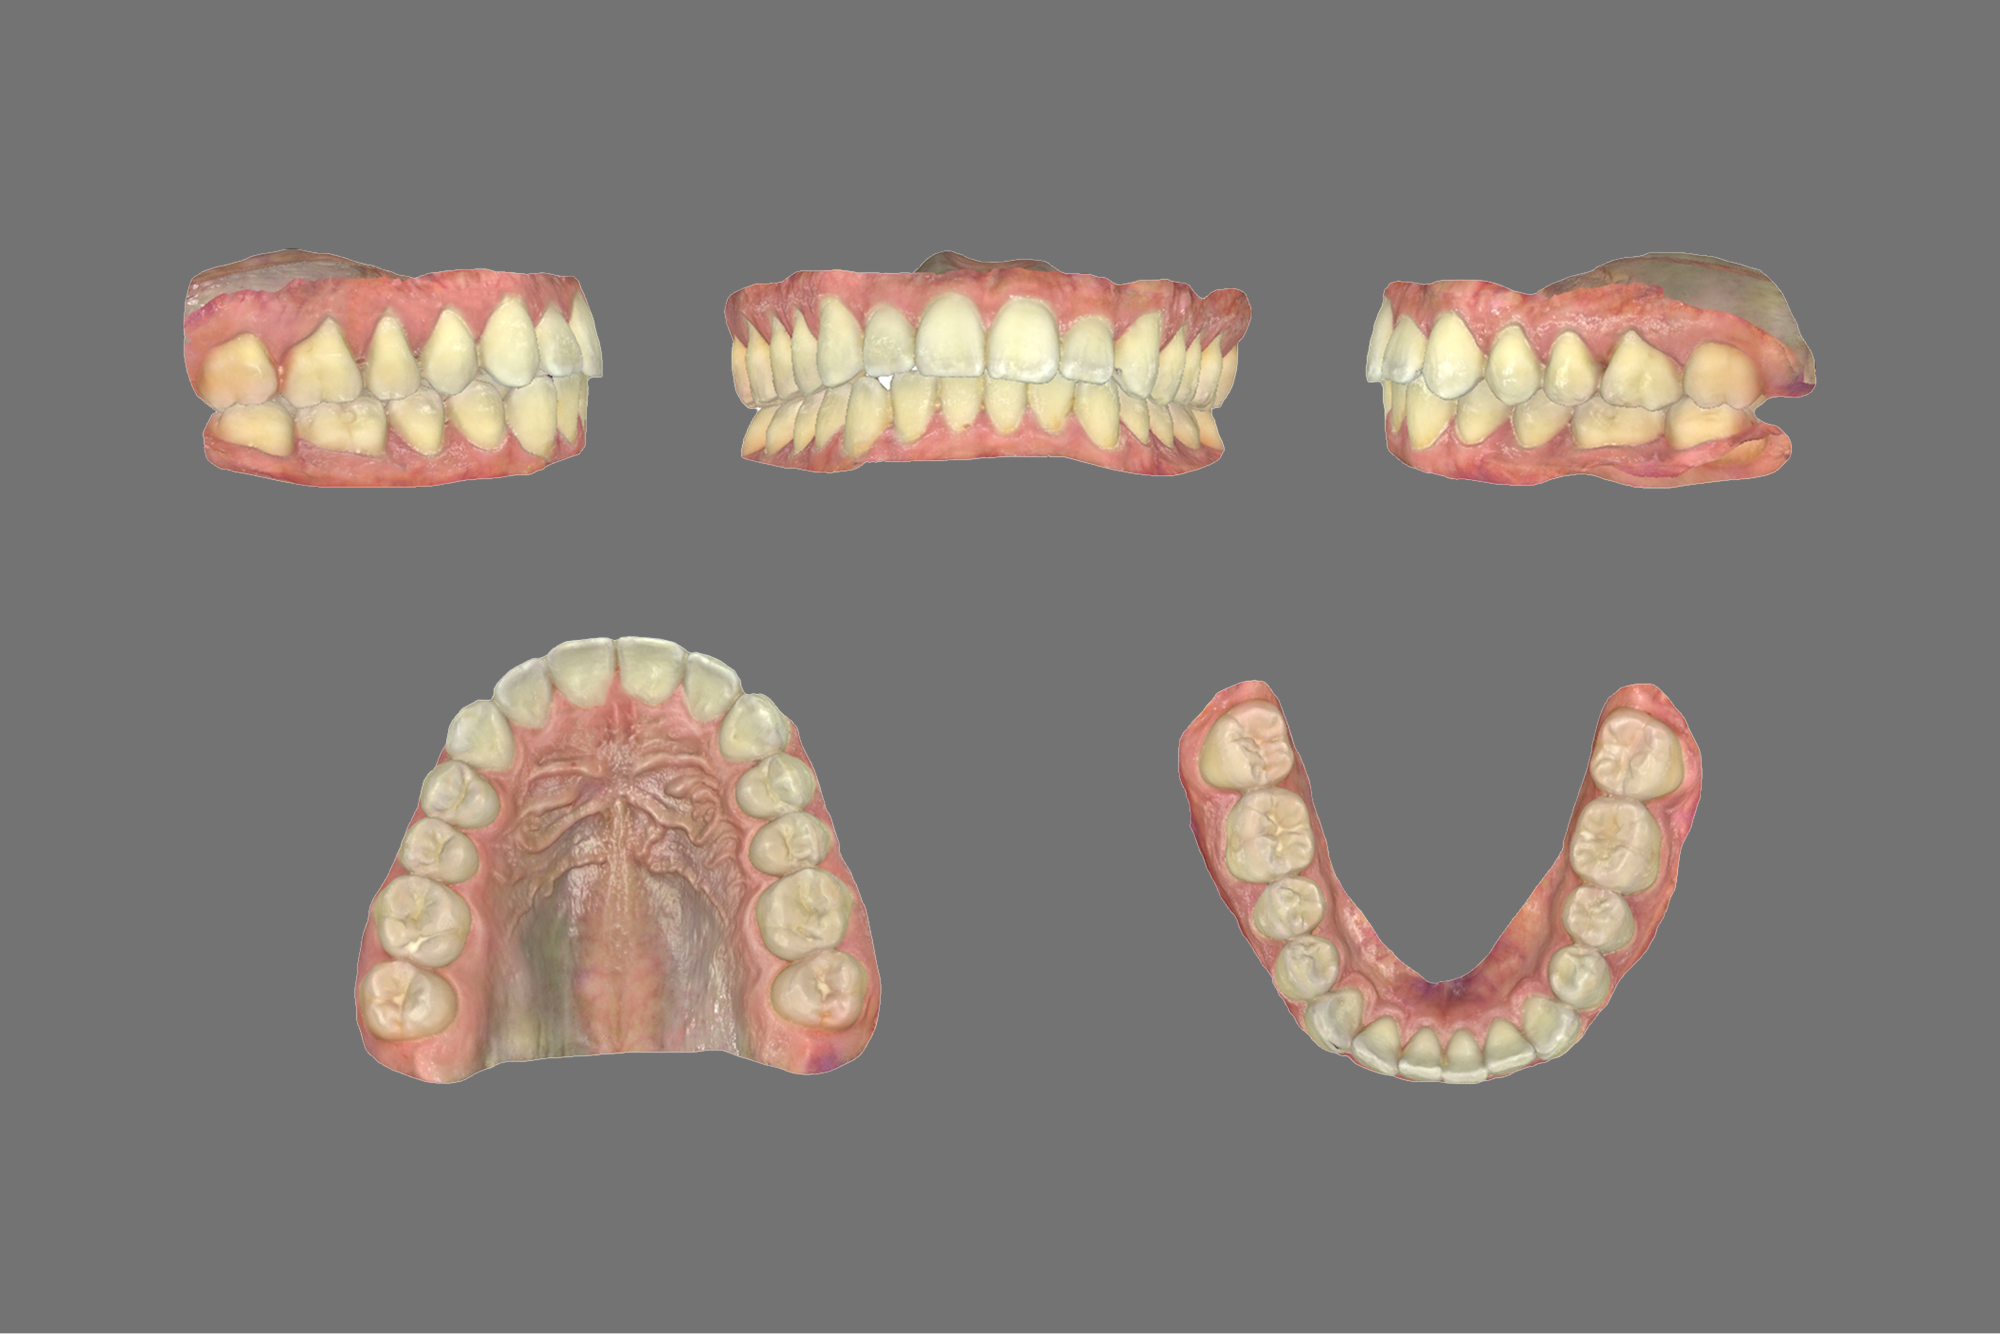

Your evaluation includes a CT scan, comprehensive oral images, sleep assessment, and personalized treatment plan from Dr. Trivedi. If you choose to proceed with the complete solution stack, your evaluation costs will be applied as a discount.

After your evaluation, the doctor reviews your results and explains how your airway structures are impacting your health. You’ll then receive a personalized plan that may include palatal expansion, aligners, or other therapies to optimize your health.